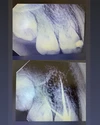

Tooth Decay

Dental and Gum Diseases

Implant Treatment